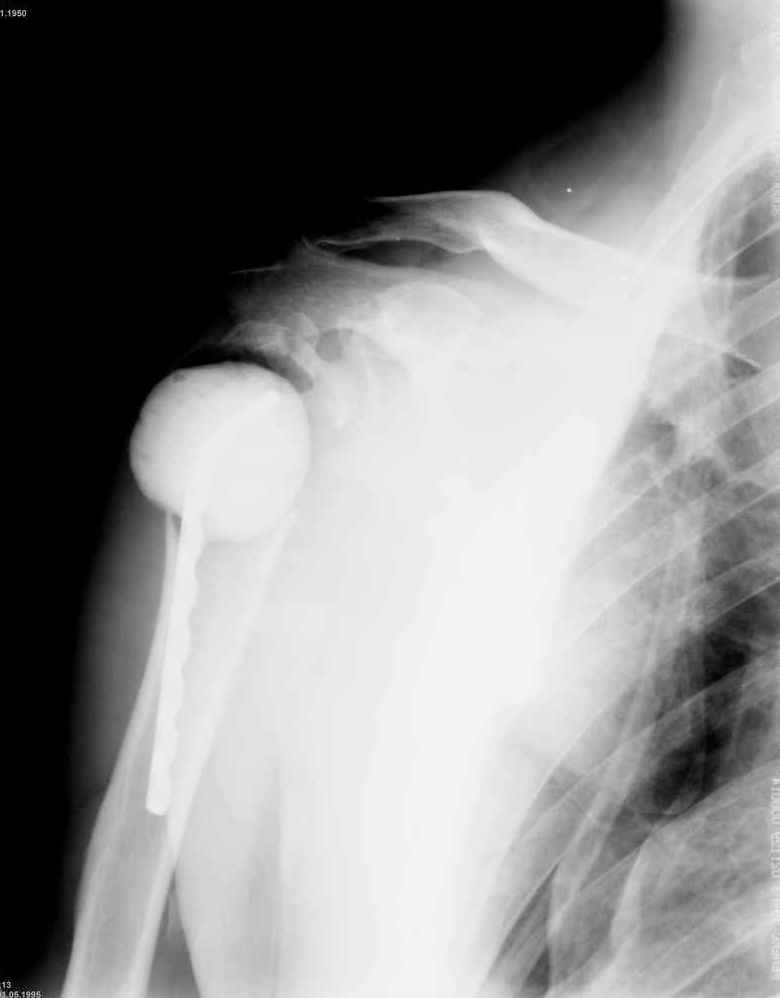

Уважаемые коллеги. Недавно из нашего отделения был выписан пациент 54 лет с закрытым переломом плечевой кости. Из анамнеза: за 2 дня до поступления в НИИСП, в состоянии алкогольного опьянения упал с лестницы на даче (высота 3-4 метра) с упором на правую руку. Через двое суток обратился за медицинской помощью. Доставлен бригадой "Скорой помощи".Правый плечевой сустав умеренно деформирован. По внутренней поверхности плеча имеется кровоподтек. При пальпации плечевого сустава имеется умеренная болезненность. Активные и пассивные движения болезненные. Снижена чувствительность по тыльной поверхности пальцев кисти и отсутствует активное разгибание кисти и пальцев. Имеется подкожная эмфизема шеи, верхней половины грудной клетки (рис 1, 2). На рентгенограмме: оскольчатый перелом головки плечевой кости со значительным смещением, перелом 2-3 ребер справа, тканевая эмфизема (рис 3). КТ при поступлении: перелом головки плечевой кости в области анатомической шейки со смещением отломка головки в грудную полость, правосторонний гидроторакс, перелом 2-3-4 ребер справа. (рис 4). Через двое суток после поступления выполнена операция: атипичная торакотомия, эвакуация свернувшегося гемоторакса, удаление инородного тела (головки плечевой кости) из плевральной полости (при этом выявлено имеющееся повреждение париетального и висцерального листков плевры) (рис. 5), дренирование плевральной полости, замещение проксимального конца плечевой кости спейсером из костного цемента с антибиотиком (рис. 6). Послеоперационный период протекал гладко. При контрольной рентгенографии положение спейсера удовлетворительное (рис. 7, 8). Дренаж из плевральной полости удален через 3 суток после вмешательства. Послеоперационная рана зажила первичным натяжением. Через 12 дней после операции больной выписан на амбулаторное лечение.

Через 3 месяца планируется повторная госпитализация для выполнения эндопротезирования правого плечевого сустава. Похожий, но менее тяжелый, случай был показан в 2004 году на сайте журнала J Bone Joint Surg Am. (http://www.jbjs.org/Image_Quiz/2004/may04/iqmay04_p1.shtml).

Я абсолютно согласен с Вами. Бугорки мы не выделяли и не фиксировали. Дело в том, что основная линия перелома проходит по анатомической шейке. И ниже нее кость повреждена, но существенного смещения осколков и бугорков до и во время операции не отмечено (прилагаю первичный снимок лучшего качества - рис. 1).

Интраоперационно было установлено, что осколки находятся примерно на своих местах и плотно связаны с окружающими тканями. Мы не стали их выделять, мобилизировать и фиксировать, так как это все равно будет необходимо сделать при установке эндопротеза.

В качестве дополнения: мы считаем, что спейсер не заменяет головку вместе с бугорками, а лишь временно заполняет свободное пространство в тканях.

После операции мы не исключали развитие пневмоторакса, плеврита, гемоторакса или эмпиемы плевры. Поэтому мы посчитали возможным заместить дефект плечевой кости спейсером с антибиотиком, а эндопротезирование выполнить в «чистых» условиях.